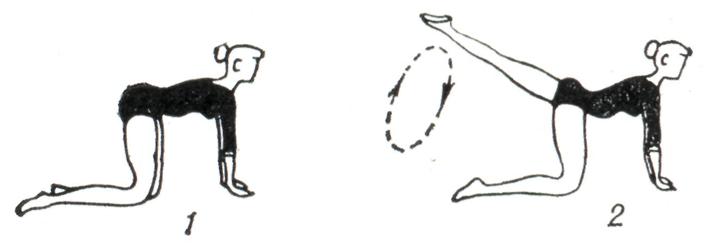

В терапии хронических артритов лечебная физкультура занимает важное место в клинической, в поликлинической и санаторно-курортной практике. При поражении суставов верхних конечностей упражнения выполняют преимущественно в положении сидя и стоя (рис. 11). При патологии суставов нижних конечностей в положении лежа, сидя и стоя тренируют опорную функцию ног (рис. 12). При заболеваниях позвоночника рекомендуют также и разгрузочные для позвоночника положения, например на четвереньках (рис. 13). Применяют упражнения активные: свободные, с усилием, с широким использованием различных снарядов, предметов и специальных приспособлений (особенно для восстановления функции кисти, в целях бытовой и трудовой реабилитации и так далее). Дополнительно используют упражнения на механотерапевтических аппаратах. Больным рекомендуется выполнение самостоятельных занятий с повторением заданий в течение дня до 4—6 раз продолжительностью по 5 — 7 мин. в целях тренировки пораженных суставов. Кроме того, полезна утренняя гигиеническая гимнастика, прогулки. Целесообразно лечебную физкультуру проводить в сочетании с массажем, бальнео- и грязелечением.

Рис. 13. | ||